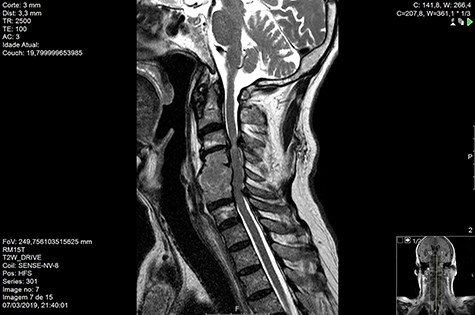

MRI and CT scans performed at 90 days post-radiation therapy showed an arrest of further progression of instability and resolution of the lytic lesion (Figs 7–13).

Computed tomography (CT) (Figs 1–3) and magnetic resonance imaging (MRI) (Figs 4–6) of the cervical spine were performed and revealed a lytic lesion involving most of C4, C5 and C6 vertebral bodies with bilateral extension to the posterior spinal elements of C4 and C5 and complete disruption of C4-C5 and C5-C6 intervertebral discs.

The Spinal Instability Neoplastic Score (SINS) [4, 6, 7] for assessing spinal instability from metastatic disease was used and the lesion was deemed unstable (SINS 13), with impending risk of increased neurological damage.